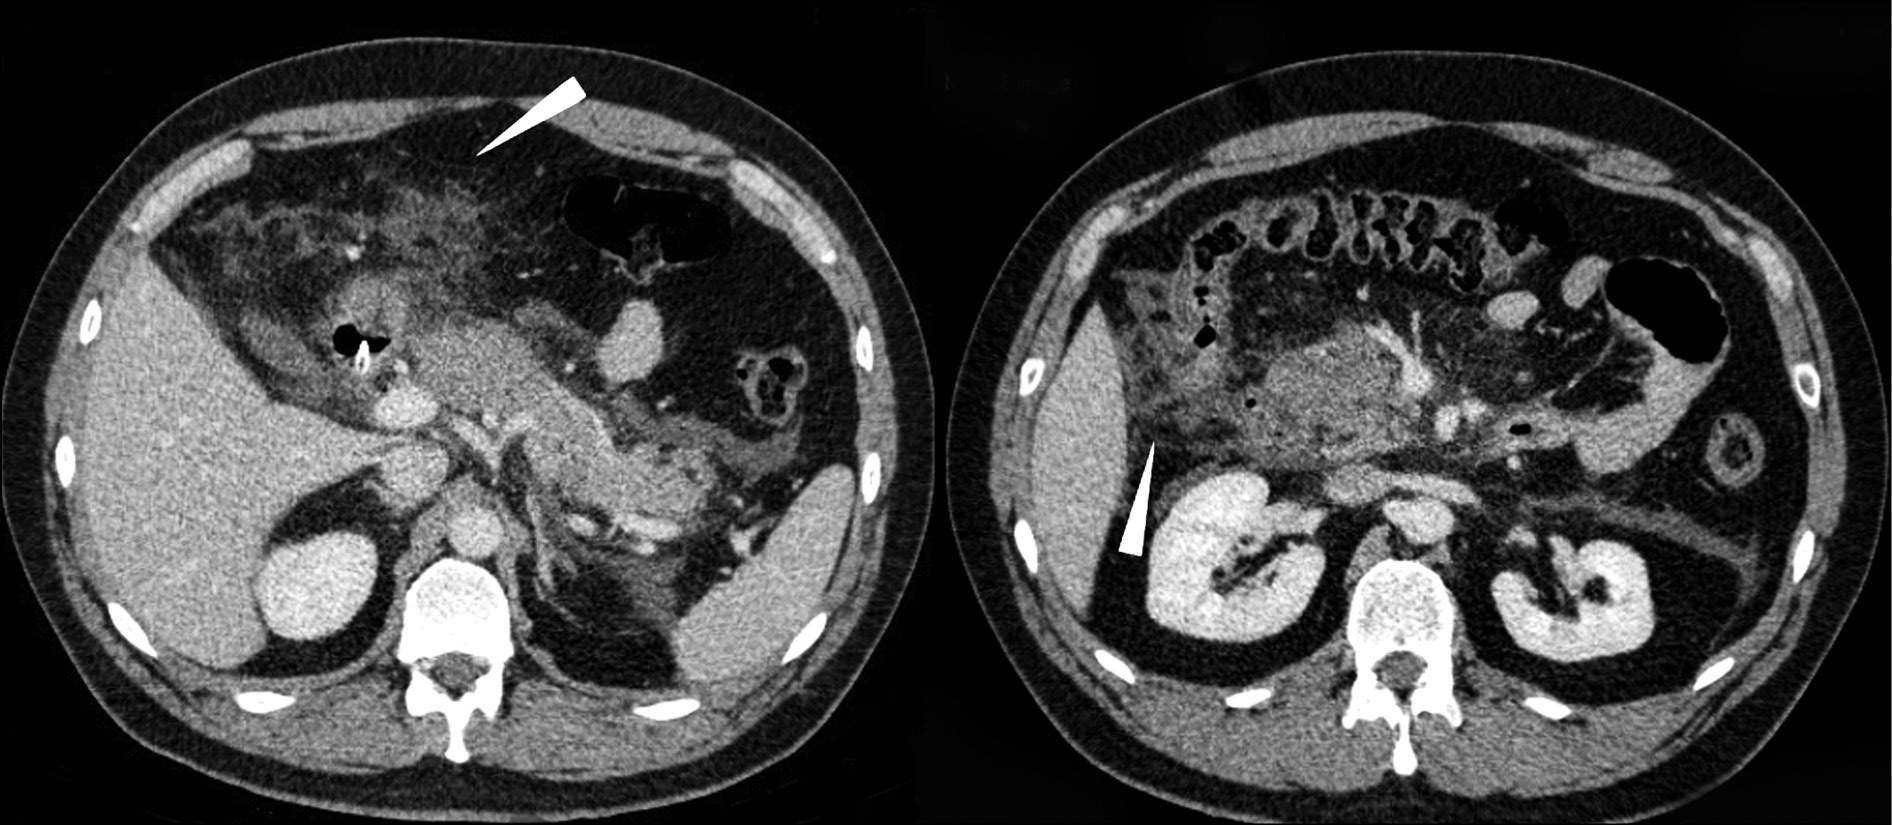

The control AO CT on March 23, 2018, detected a decrease in the size of the infiltrate anterior to the body and tail of the pancreas, as well as a decrease in the infiltrate along the ascending colon; the gland was reduced in size, with the sagittal size of 17 mm at the level of the tail and 6 mm at the level of the body, and it was not significantly differentiated at the level of the gland head (Fig. 6).

Fig. 6. Computed tomography of abdominal organs with intravenous contrast: drainage tube (image on the left, arrow); precipitated infiltration and fluid accumulation in peripancreatic adipose tissue, decreased in dynamics (image on the right, arrow).